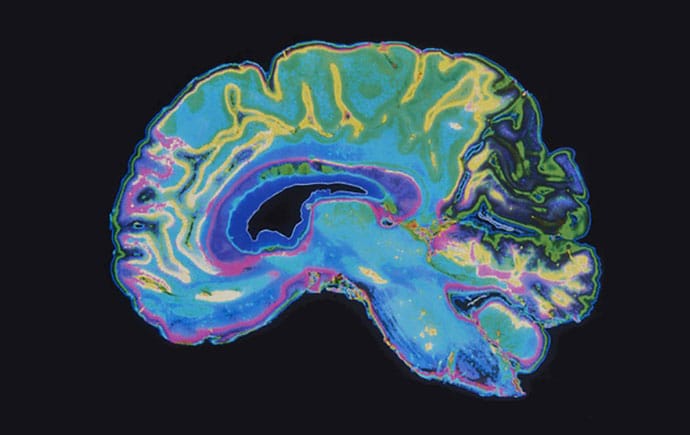

🧠 How Psilocybin Affects the Brain

Psilocybin has been shown to act on brain regions associated with mood, cognition, and perception. And early research studies linked it to changes that could help the brain become more flexible and adaptive to change over time.

A pivotal study back in 2021 found that a single dose of psilocybin increased the growth of connections between brain cells in mice, and those changes lasted for weeks.

Recent human studies suggest psilocybin may also temporarily alter how different brain networks communicate, which is why researchers think these mechanisms may help interrupt stuck patterns of thinking and feeling, offering a window of change for those who seek it.

And larger comprehensive review papers describe psychedelics as possible “psychoplastogens,” which are substances that can help the brain become more open to change and rewiring.